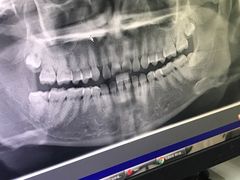

• 青岛市口腔医院(总院)

• -青岛市口腔医院(总院)